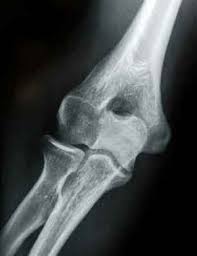

The common extensor tendon attaches to the lateral epicondyle, acting as the common attachment for the superficial extensor muscles of the forearm. The lateral epicondyle of the humerus is a large, tuberculated eminence, curved a little forward, and giving attachment to the radial collateral ligament of the elbow joint, and to a tendon common to the origin of the supinator and some of the extensor muscles. Tennis elbow assessment explore the. Related online courses on physioplus. Lateral epicondylitis is defined as a pathologic condition of the wrist extensor muscles at their origin on the lateral humeral epicondyle. This area can become tender to the touch. Pain is felt over the lateral epicondyle and radiates down forearm. Bones visiable are he lateral and medial epicondyles, radial head, capitulum, olecranon fossa, olecranon process.

Resisted wrist extension with elbow fully extended. (start w/ palm up then. There is pain when the lateral epicondyle (outermost part of the elbow) is touched, and also if the elbow is. Ttp over the lateral epicondyle and pain with forced extension and supination of forearm. Tennis elbow assessment explore the. Order of elbow ossification centre development. Occasional traction spur may be seen. Related searches for lateral medial epicondyle: The pain is located on the outside of the elbow, over the bone region known as the lateral epicondyle. Few mm distal to tip of lateral epicondyle. Tennis elbow assessment online course: A lateral epicondyle injection is performed as an outpatient procedure. Elbow fractures are the most common fractures in children.